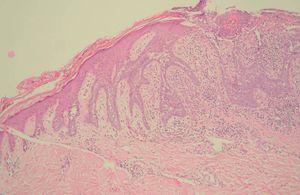

El paciente acudió a consulta por la aparición de tres pápulas de coloración carnosa sobre el nevo sebáceo (fig. 1). Se procedió a la extirpación de estas lesiones y el estudio histológico mostró la aparición de agregados de células basaloides organizados en islotes celulares que fueron diagnosticados de carcinomas basocelulares. En una de ellas, la simetría, el aspecto claramente circunscrito de la lesión y la presencia de una grieta de retracción entre el estroma tumoral y la dermis adyacente planteó la posibilidad de un tricoblastoma, aunque la disposición del tumor con su eje mayor en sentido horizontal, así como el predominio del componente epitelial sobre el estromal entre otros, llevó al diagnóstico final de carcinoma basocelular, aunque con un componente hamartomatoso (fig. 2). En las otras dos lesiones, los islotes de células basaloides que colgaban de la epidermis, así como la asimetría y la ulceración llevaron al diagnóstico de carcinoma basocelular (fig. 3).

Fig. 3.--Proliferación multicéntrica de células basaloides junto con ulceración en la zona central de la lesión. (Hematoxilina-eosina, x 40.)